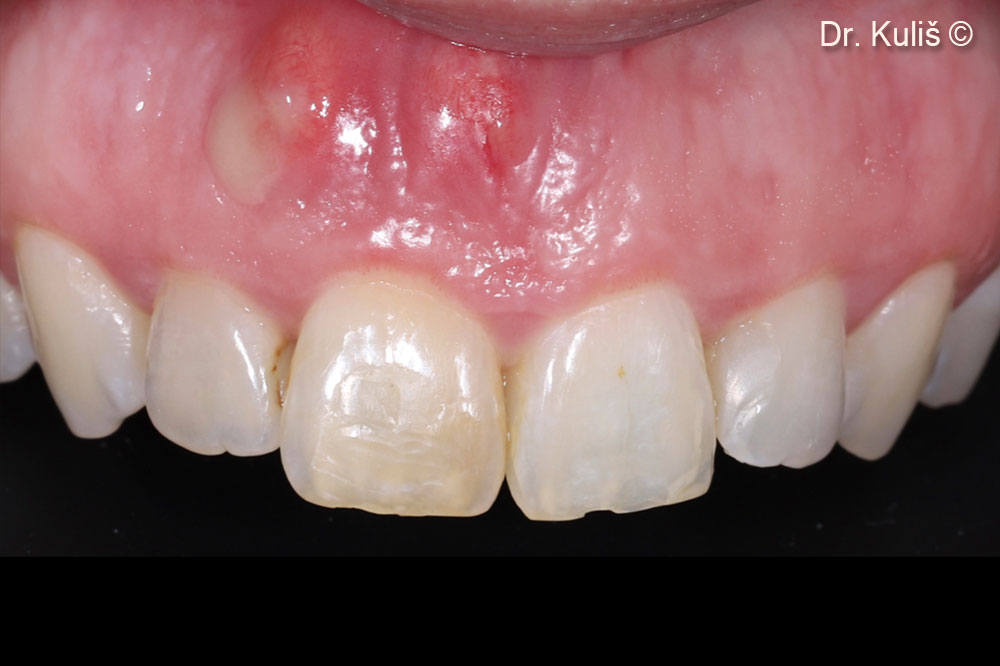

Một bệnh nhân nữ (33 tuổi) có tổn thương quanh chóp răng cửa giữa bên phải.

Tình trạng ban đầu. Dịch mủ do tổn thương quanh chóp răng cửa giữa bên phải.